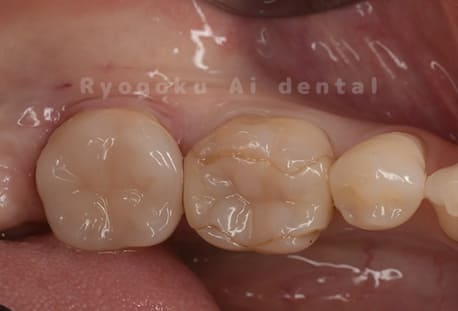

Case07

-

- 原因

- 虫歯

- 治療内容

- セラミッククラウン

- 治療費用

- 110,000円

銀歯が浮いた感じがする、と相談された患者さんです。銀歯を外し、虫歯治療を行い、セラミックの被せ物で治療を行いました。

<リスク・副作用>

過度の咬合や衝撃で割れることがあります。